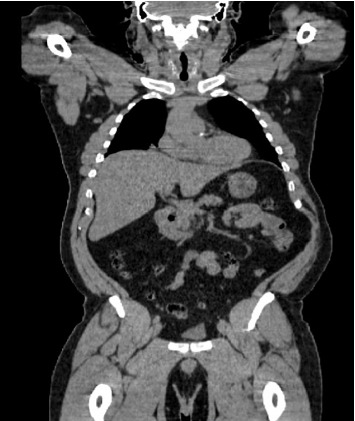

肾细胞癌(RCC)的幸存者,特别是肾切除术后,需要长期随访复发或全身并发症。当有肾细胞癌病史的患者出现肺结节时,我们必须考虑到感染性疾病,特别是那些环境暴露和与肾切除术后继发代谢变化相关的免疫改变的患者。我们报告了一位49岁男性患者,他在肾切除术后患有肾小细胞癌,有长期吸烟史,并有明显的煤尘暴露史,他发展为进行性肺结节。虽然最初怀疑为转移性肾细胞癌(mRCC),但连续影像学显示结节增大,PET扫描无代谢活动,需要进一步评估。鉴于持续的呼吸道症状,他接受了支气管镜检查并进行了微生物学分析,发现了烟熏曲霉,最终被诊断为慢性肺曲霉病。我们的患者成功地用伏立康唑治疗,并随着时间的推移显示出显著的临床改善。在本例中,我们观察了RCC幸存者肺结节的诊断困境,以及广泛鉴别以避免误诊的重要性。肾切除术后的免疫变化,可能伴有慢性肾脏疾病(CKD),或长期的肿瘤监测可能使患者处于机会性感染的危险之中。为了确保及时发现和治疗可能模拟肿瘤进展的感染,临床医生治疗RCC幸存者应将微生物学诊断纳入常规肺部评估。

Survivors of renal cell carcinoma (RCC), especially following nephrectomy, require long follow-up for recurrence or systemic complications. While those with a history of RCC develop pulmonary nodules often with concern for metastasis, we must consider infectious diseases, especially in patients with environmental exposures and immune alterations related to metabolic changes secondary to nephrectomy. We report a 49-year-old male with a history of RCC status postnephrectomy, history of long-term smoking, and history of significant coal dust exposure, who developed progressive pulmonary nodules. Although initially suspected to be metastatic RCC (mRCC), serial imaging demonstrated nodule enlargement without metabolic activity on PET scan, requiring further evaluation. Given the persistent respiratory symptoms, he underwent bronchoscopy with microbiologic analysis which identified Aspergillus fumigates and was ultimately diagnosed with chronic pulmonary aspergillosis. Our patient was successfully treated with voriconazole and over time demonstrated significant clinical improvement. In this case, we have made the observation of the diagnostic dilemma presented by the pulmonary nodules in RCC survivors and the importance of a broad differential to avoid misdiagnosis. Immune changes following nephrectomy, possible accompanying chronic kidney disease (CKD), or prolonged oncologic surveillance could place patients at risk for opportunistic infections. In order to ensure timely detection and treatment of infections that may mimic tumor progression, clinicians treating RCC survivors should integrate microbiologic diagnostics into routine pulmonary evaluations.